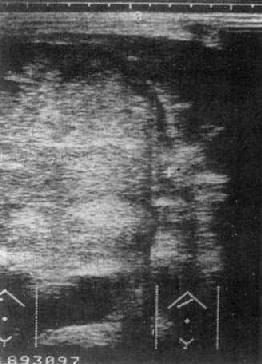

原发性肝癌:USG是影像学诊断中的首选方法。声像图上肝癌表现为聚集成团的强回声区,光团强弱分布不均,边比缘不规则。光点常粗糙明亮,与正常肝组织有明显差别。肿瘤区下方的正常肝组织回声强度降低,系因肝癌引起的超声衰减所致(图4-3-2)。

肝癌(巨块型)

图4-3-2 肝癌(巨块型)